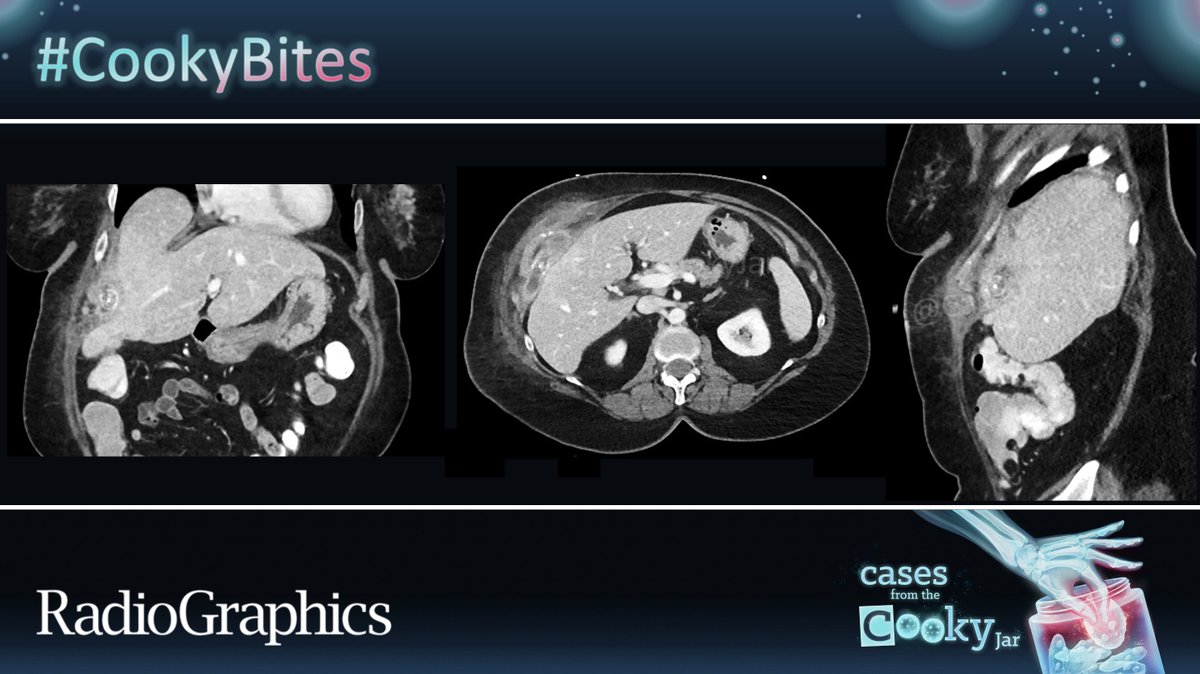

55 M presents with fever and abdominal pain post-cholecystectomy. What is the diagnosis? 🧐🔍 We’ll post the answer in 24h. Share companion cases with us using #CookyBites #241. We will RT the best cases! #RGphx @cookyscan1 @RadioGraphics

69 F with colon carcinoma in remission post resection, MASLD and kidney failure due to DM type 2, currently on insulin presents with mass-like lesion in the abdomen. Diagnosis ⁉️ Answer: 🔗 Have a companion case? Share using #CookyBites #240. We will RT the best cases! #RGphx